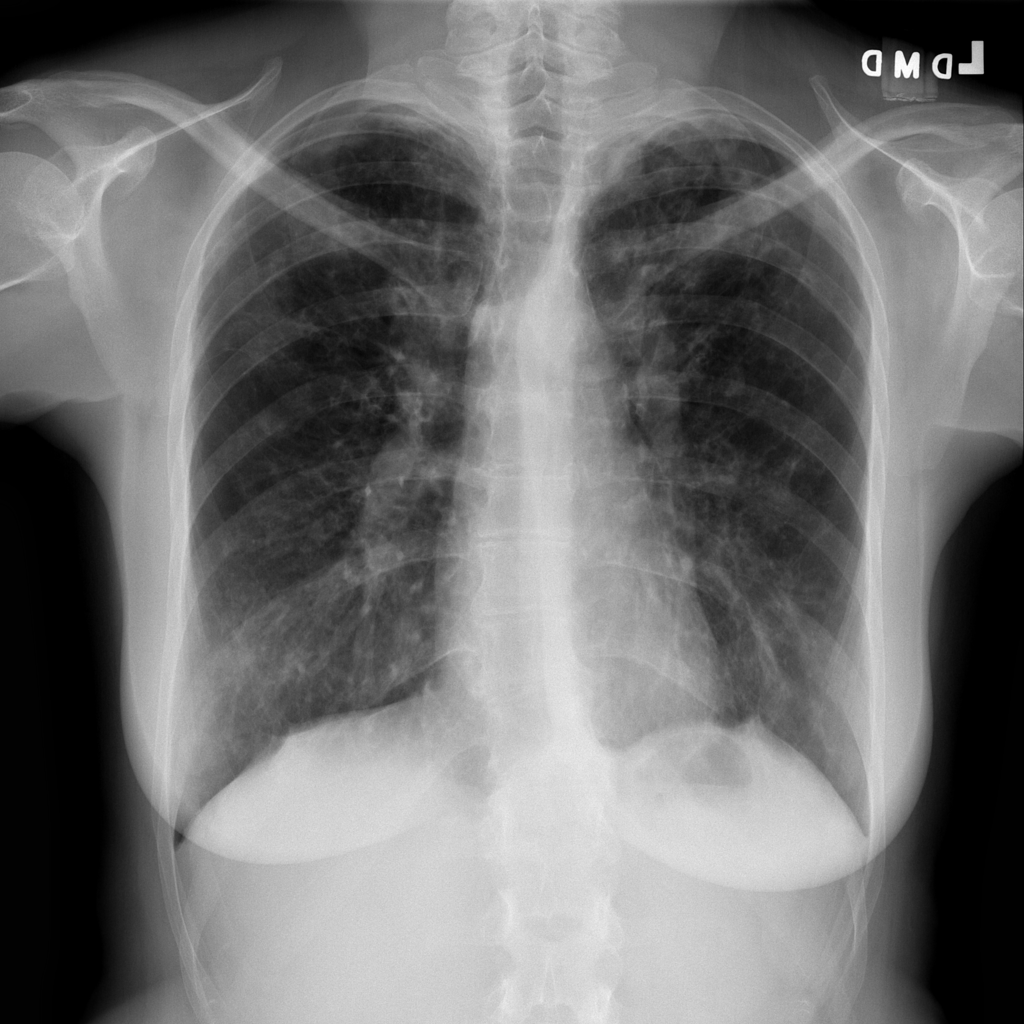

Showing up to 90 reference images for Nodule.

PAT-250B · IMG-000Nodule

PAT-250B · IMG-000

PA